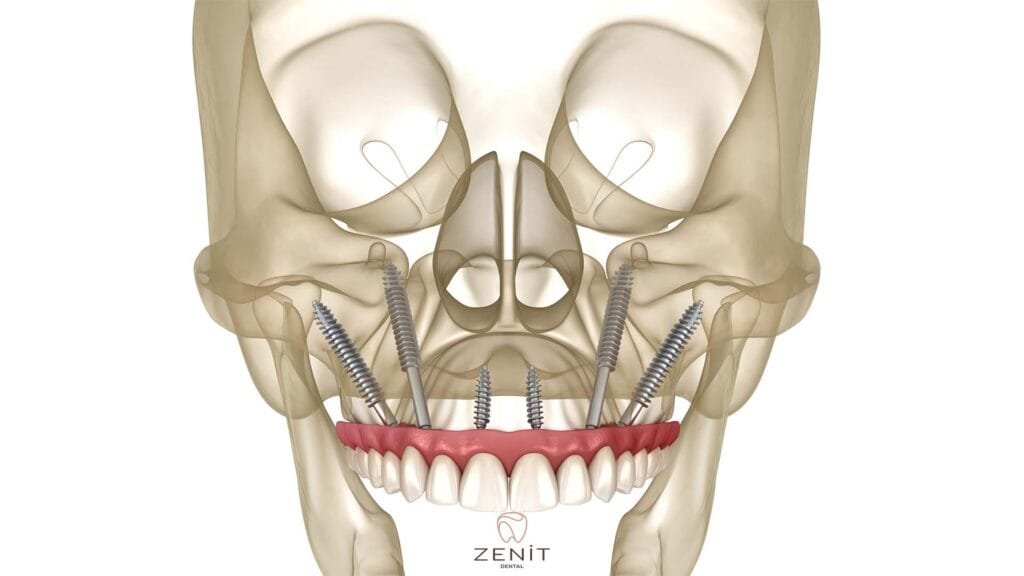

Zygoma implants offer an excellent alternative for patients with inadequate jawbone and provide a revolutionary treatment in the facial area. These special implants, unlike traditional implants, are placed in the zygomatic (zygoma) bone instead of the upper jaw bone. Since the zygomatic bone has a denser and stronger structure than the jawbone, zygoma implants can be safely placed in this area. Thanks to zygoma implants, even patients with advanced bone loss can achieve aesthetically and functionally satisfactory results.

Zygoma implants, unlike the traditional placement methods of dental implants, are implants specially designed for patients with jaw bone deficiency. Generally, in cases of jaw bone deficiency, it may be difficult to place an implant, especially in the upper jaw area. In this case, zygoma implants come into play.

Zygoma implants placed in the cheekbone, unlike other dental implants, are placed not in the jawbone, but in the area called zygomatic bone, which is located in the middle of the face and has a very solid structure. The zygomatic bone has a denser structure than other bones and bone loss usually does not occur. Thanks to this feature, zygoma implants offer a safe and effective solution to patients with jaw bone deficiency.

- Implant Placement: Zygoma implants are placed in the cheekbone instead of the upper jawbone. The surgeon works with high precision when placing the implants, because reaching the zygomatic area and placing the implants in the correct position requires great care.